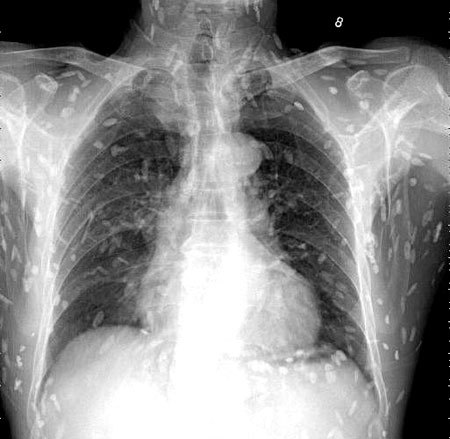

브라질의 한 의료진이 소셜네트워크서비스(SNS)에 기생충에 감염된 엑스레이 사진을 공개했습니다. 사진에는 몸속에 있는 기생충이 죽어 석회화된 수백 개의 점 형상이 보였습니다.

특히 유충이 근육이나 뇌 조직에 침투한 모습은 매우 충격적이었습니다. 이러한 증상은 유구조충의 유충에 의한 인체감염증으로, 유구 낭미충증이라고도 불립니다.

의료진은 해당 환자가 특별한 치료를 받지 않았다고 밝혔습니다. 그는 "머리, 척수, 눈에 이상이 없는 한 치료가 필요하지 않습니다"라며 "해당 물체들은 석회화되어 있어 생존 가능한 유충이 아닙니다. 불편함을 느끼지 않는다면 특별한 조치가 필요하지 않습니다"라고 말했습니다. 그러나 해당 환자의 뇌에 낭종이 있는지 확인하기 위해 MRI 검사를 기다리고 있다고 전했습니다.